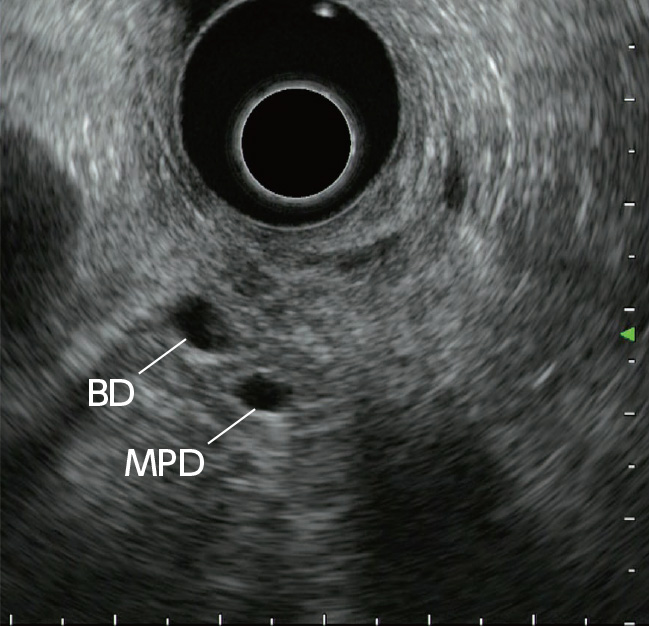

STEP 3 | Distal bile duct

While rotating the scope clockwise, advance it slowly. Observe the head of the pancreas while following the bile duct towards the papilla. At this time, the main pancreatic duct is imaged on the distal side of the bile duct.

The trick to visualizing the papilla is to inject lukewarm water into the descending part of the duodenum so that the region can be observed, while maintaining some distance between the transducer and the papilla. This can be achieved by applying down and left angulation. After the cross-sectional views of the bile and pancreatic ducts (Fig. a) have been visualized, the short-axis view of the papilla (Fig. b) can be visualized continuously in the six o’clock direction from the transducer. Then slowly rotate the scope counterclockwise while bending the scope tip up to visualize the long-axis view of the papilla and vicinity (Fig. c) , as well as the cross-sectional views of the bile and pancreatic ducts (Fig. d).